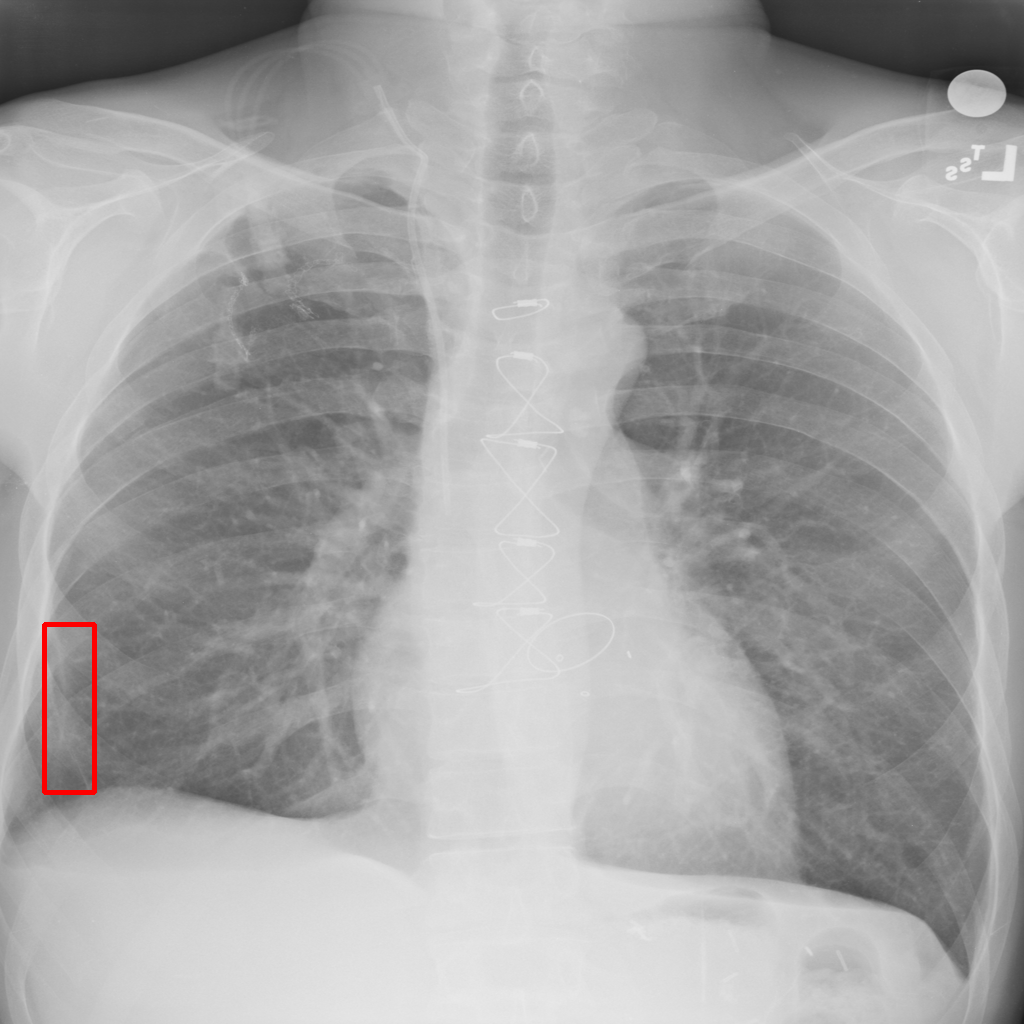

Object Rotation

X-ray GMAIMMbench Disease Diagnosis

Object Rotation - L0 (Original)

L0

L0 (Original)

Question

Given the boxed region in the X-ray image, which abnormality is the image most indicative of?

A pneumothorax B pulmonary fibrosis C bone fracture D pleural effusion

Ground Truth: A. pneumothorax